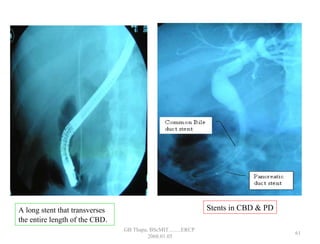

A long stent that transverses

the entire length of the CBD.

Stents in CBD & PD

• 56.

A long stentthat transverses the entire length of the CBD. Stents in CBD & PD 61 GB Thapa, BScMIT.........ERCP 2068.01.05